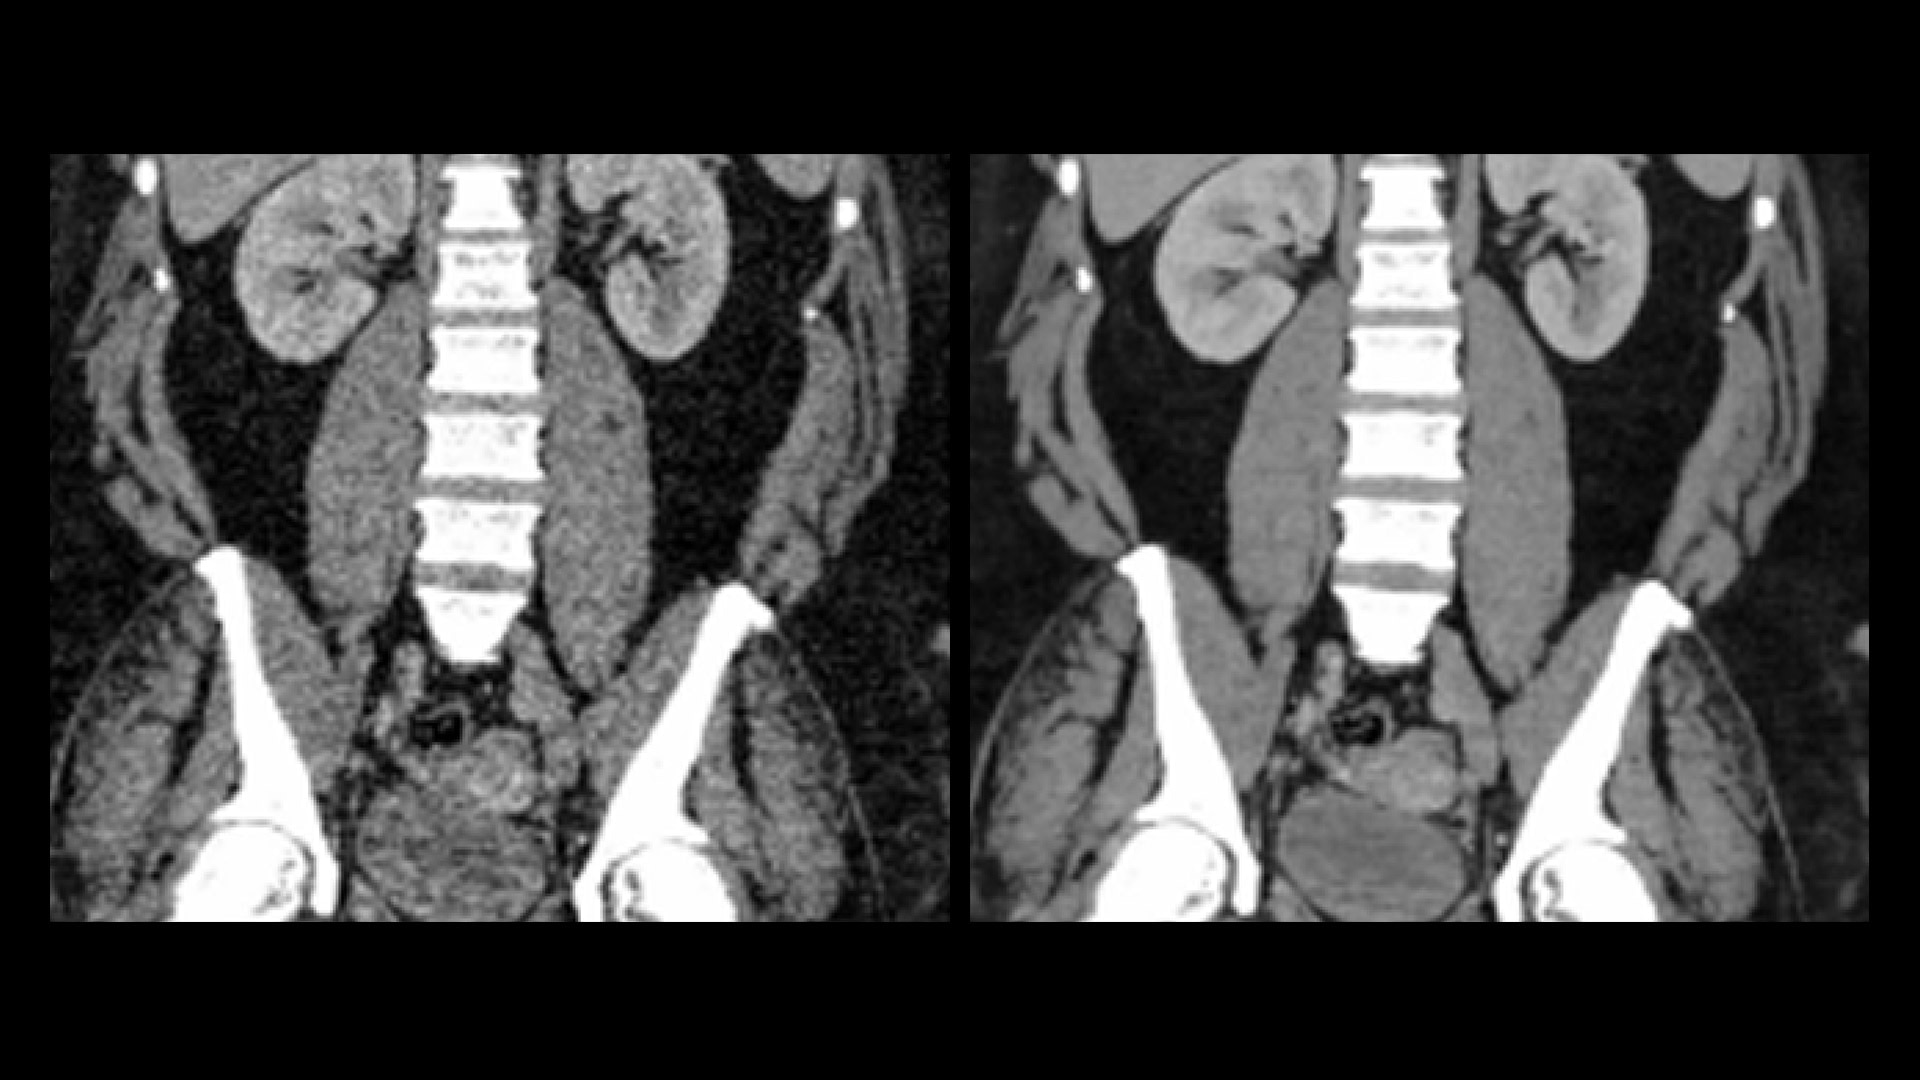

Effortless Recon DL

A portfolio of deep-learning applications designed to easily and quickly acquire and construct exceptionally clear images for confident decision making.

2. TrueFidelity

As demonstrated in a clinical evaluation consisting of 60 cases and 9 physicians, where each case was reconstructed with both TrueFidelity and ASiR‐V and evaluated by 3 of the physicians. In 91% of the reads, TrueFidelity noise texture was rated better than ASiR‐V’s. This rating was based on each individual reader’s preference.